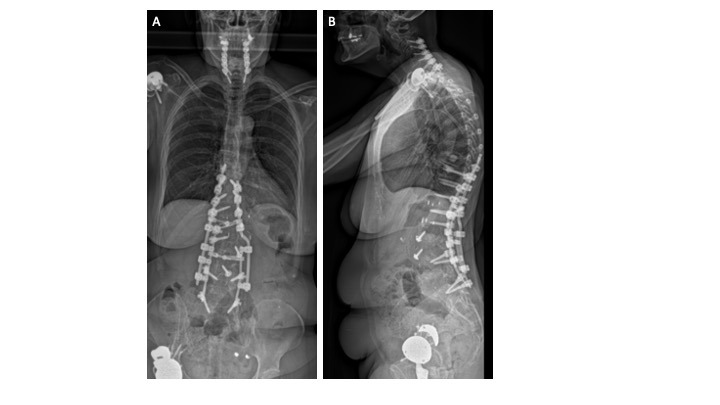

In addition to the multiple revision THAs, our patient was concomitantly being treated for continued sagittal plane imbalance and spinal stenosis. In August 2016, the patient underwent posterior instrumentation of the T9-L4 vertebrae as well as direct lateral interbody fusion of the T12-L2 disc spaces. In July 2018, the patient underwent cervical instrumentation of the C3-T1 vertebrae to treat myelopathy, which was extended to include C2-C3 anterior/posterior spinal fusion in September 2020 to address instability. Erect, lateral spine radiographs were recorded and demonstrate a pelvic incidence of 54ºwith a pre-operative lumbar lordosis of 33º (PI-LL mismatch of 21º indicating a severe sagittal spinal deformity) and a post-operative lordosis of 46.9º. (Figures 9a-b) While these radiographs represent a physiological alignment, the resulting stiffness could explain the recurrent THA instability.